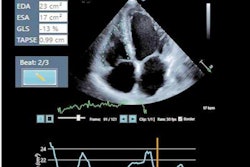

Under the deal, DiA's LVivo Toolbox automated cardiac analysis software will be integrated into Terason's point-of-care ultrasound devices, according to the vendors.